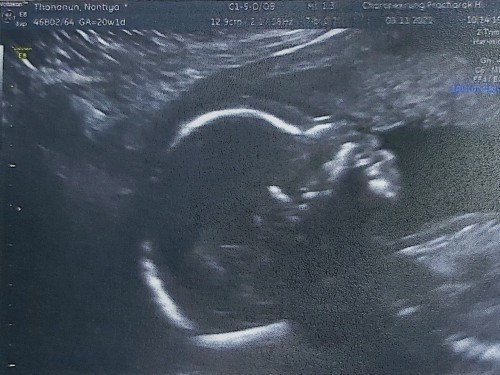

อัลตร้าซาวด์ครั้งแรก 20 Weeks

คุณหมอนัด อัลตร้าซาวด์ครั้งแรก ตื่นเต้นมากๆ นึกว่าจะไม่รู้เพศ สรุปลูกชายคร้า 😊 ดีใจ แต่คุณหมอบอกนัดซาวด์เดือนหน้าอีกรอบเพื่อดูหัวใจ เพราะคุณลูกชายดิ้นตลอดการซาวด์ไม่หยุดจนคุณหมอบอกให้คุณบอกลูกให้หยุดที 😂 หนูคึกมากเลย#ท้องแรกคะ